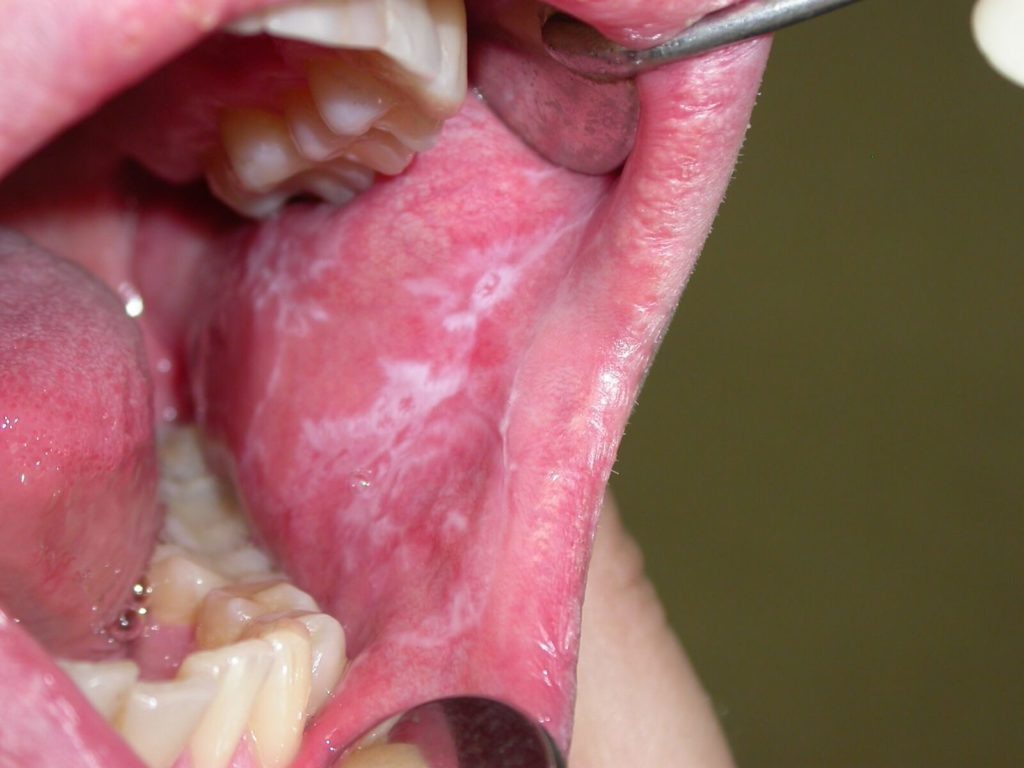

Разделенная на две части внутреннюю и наружную сторону губа имеет очень тонкую, нежную и довольно уязвимую поверхность. Спровоцировать случаи, когда появляются язвочки на внутренней стороне губы, может высокая чувствительность и главная причина – нарушение барьерной функции слизистой. Часто дефект слизистой появляется в таком виде, как на изображении ниже. Это язва внутри губы фото с ранкой, покрытой светлым налетом.

Невидимый процесс воспаления, а точнее сказать борьбы с болезнетворными микроорганизмами в организме тяжело проходит для человека. Чаще всего это проявления стоматита. Ниже можно посмотреть, как выглядят язвы на губах фото, демонстрирует состояние на второй день, от начала их формирования.

Белый налет на измененной слизистой, внутренняя часть губ